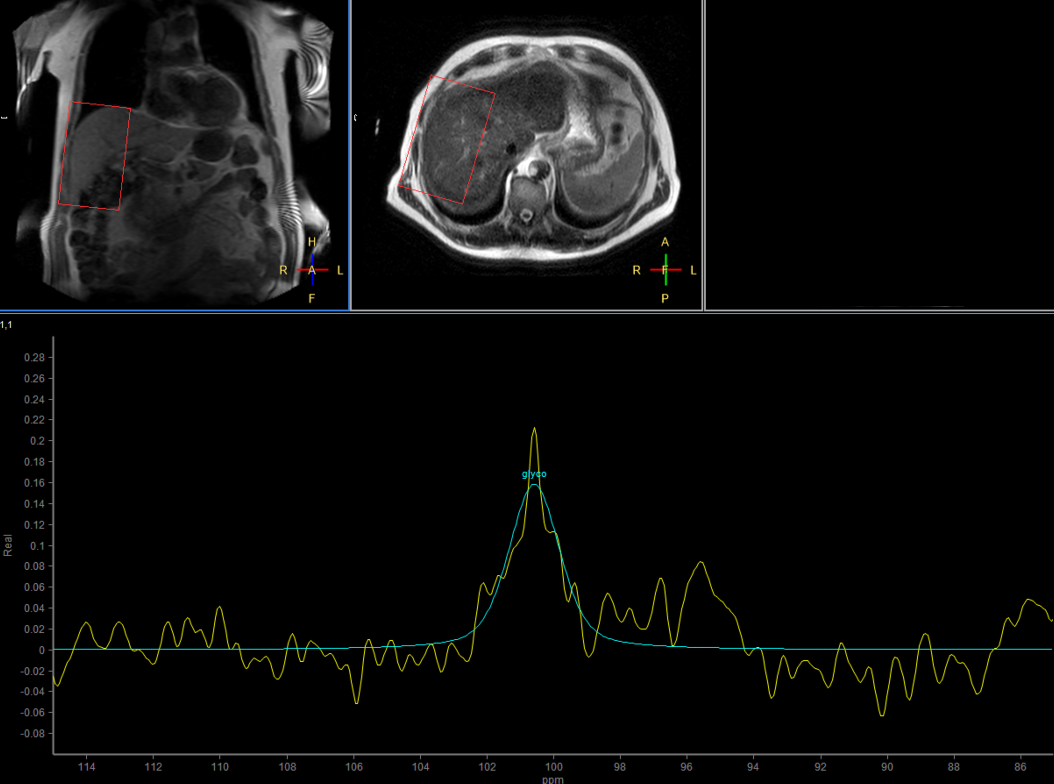

Multi Nuclei - Liver imaging (13C)

Make multi-nuclei imaging and spectroscopy become part of your clinical operations via a seamless integrated workflow for multi-nuclei image acquisition, spectroscopy, reconstruction, and viewing. The nucleus is just a scan parameter like any other sequence parameter. A single ExamCard can be used to run both proton and non-proton imaging. Reconstruction and viewing of non-proton images or spectra, as well as the process for sending the data to PACS is fully integrated, so workflow does not differ from proton imaging. The transmit-receive 13C flex coil, with a 14 cm diameter, is immediately recognized by the ExamCard interface. Improved SNR and simplified spectra* are achieved by combining body coil decoupling with the transmit-receive surface coils.